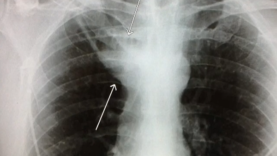

What is a Tension Pneumothorax? | Lecturio Emergency Medicine Mediube Subscribe Subscribed 3 1173 videos 0% 29 Views 0 Likes 2024-04-18 Pulmonology By Mediube 0 Comments (بازدید 29 بار, بازدیدهای امروز 1 ) Show more PREV Pneumothorax for Nursing(collapsed lung) Animation, Treatment, Decompression, Pathophysiology Mediube 2024-04-16 NEXT Tension Pneumothorax Emergency Medicine | Lecturio Mediube 2024-04-18 You might be interested in 0 Anatomy and physiology of the respiratory system Mediube 2024-09-18 0 An introduction to chest CT scanning – anatomy and approach Mediube 2024-01-31 0 What Is Severe Asthma؟ Mediube 2024-05-25 0 Lung Anatomy Mediube 2024-09-22 0 CDC Tuberculosis (TB) Transmission and Pathogenesis Mediube 2024-10-02 0 How to auscultate lung sounds Mediube 2024-01-31 0 Pneumothorax vs Lung Collapse Mediube 2024-04-15 0 What Happens During a CT Lung Scan Mediube 2024-06-06 0 Thoracentesis Mediube 2024-04-27 0 Lung Transplant Patient Journey Mediube 2024-10-02 0 Tuberculosis – causes, symptoms, diagnosis, treatment, pathology Mediube 2024-10-12 0 How to identify normal lung anatomy on chest CT Mediube 2024-06-06 LEAVE YOUR COMMENT Cancel replyYour email address will not be published. Required fields are marked * Save my name, email, and website in this browser for the next time I comment. Δ